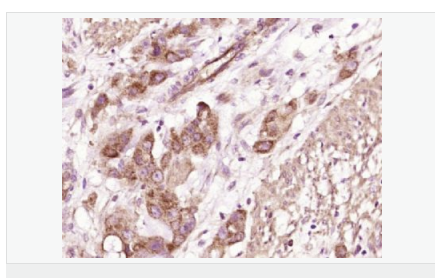

| 產品應用 | WB=1:500-2000 ELISA=1:5000-10000 IHC-P=1:100-500 IHC-F=1:100-500 ICC=1:100-500 IF=1:100-500 (石蠟切片需做抗原修復) not yet tested in other applications. optimal dilutions/concentrations should be determined by the end user. |